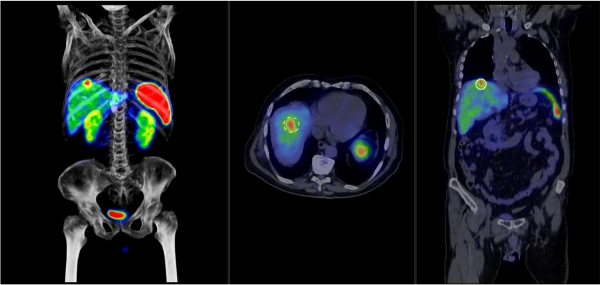

AnyScan TRIO® SPECT/CT tasvirlash tizimi ideal SPECT piksellar sonini va yuqori tasvir sifatini murosasiz taqdim etadi. Noyob uch boshli detektor dizayni suratga olish vaqtini qisqartirish orqali batafsil tasvirlarni olish imkonini beradi. Tizim qo'shimcha KT quyi tizimi bilan yadroviy tibbiyot uchun ideal multimodal uskunaga aylanadi. Ko'p teshikli kollimatsiya qo'shilishi bilan AnyScan TRIO® tizimi molekulyar tasvirlashda yangi zamin yaratadi. Xususiyatlari va afzalliklari Optimallashtirilgan vaqt-sifat-doza Klinik yadroviy tibbiyot amaliyoti tasvir sifatini buzmasdan tasvirni olish vaqtini sezilarli darajada qisqartirishi mumkin bo'lgan yuqori samarali tasvirlash tizimlarini talab qiladi. Bu mutlaqo mantiqiy so'rov va bizning javobimiz AnyScan TRIO® SPECT/CT multimodal tasvirlash tizimidir. Qisqartirilgan tasvirni olish vaqti: O'rtacha tasvirni olish vaqtini chorakgacha qisqartirish mumkin. Butun tananing SPECT/CT suyak skanerlashi 20 daqiqadan kamroq vaqt ichida bajarilishi mumkin. Rasmni olish vaqtini qisqartirish bemorning qulayligini yaxshilashga yordam beradi va harakat artefaktlari ehtimolini kamaytiradi. Tasvirning maksimal sifati: diagnostika aniqligi va ishonchliligini oshiradi. An'anaviy qo'sh detektorli boshga o'rnatilgan SPECT tizimlariga nisbatan sezilarli darajada yuqori tizim ruxsati va kontrast-shovqin nisbati ikki baravar yuqori. Kamaytirilgan ma'mur yuki: bemorning nurlanish dozasini kamaytiradi va administrator xavfini kamaytiradi. Amaldagi izlagichlarning kamroq soni radioaktiv izlagichlarning o'rtacha narxini dinamik ravishda kamaytirish imkonini beradi.